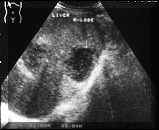

An

abscess

of

recent

onset

has

a

distinct

central

liquified

area.

This

is

seen

on

ultrasound

as

sonolucent

or

hypoechoic

area

usually

with

fine

internal

echoes.

Because

the

liquefaction,

there

associated

posterior

acoustic

enhancement.

cavity

may

be

round,

oval

branching.

walls

at

stage

are

not

very

thick

and

sometimes

demarcation

between

wall

surrounding

tissue

can

poor.

thicker

these

shaggy,

ill-defined

echogenic

areas

along

(see

Picture2).

It